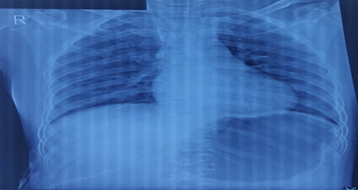

To arrive at a definitive, contrast enhanced CT (CECT) of whole abdomen was done which revealed mildly enhancing right adrenal mass with areas of hemorrhage and necrosis; adrenocortical carcinoma, metastasis and lipid poor adenoma with internal hemorrhage were the suspected radiological differentials. Apart from that, enlarged bilateral kidneys with numerous cyst (Bosniak category 1) diffusely involving bilateral renal parenchyma were seen suggestive of autosomal dominant polycystic kidney morphology and there was presence of simple hepatic cysts.Similarly, CECT chest revealed right suprarenal solid cystic mass lesion with indeterminate washout pattern highly suggestive of pheochromocytoma. On further biochemical evaluation, 24-hour urinalysis was done which revealed raised metanephrines (>10000 mcg/day) and normetanephrine (>6397.87 mcg/day) arriving at a definitive diagnosis of pheochromocytoma. Chest X-ray of the patient revealed enlarged left ventricle which can be explained by increased after-load secondary to chronic uncontrolled hypertension (Figure 1). Similarly, electrocardiography also showed the features of left ventricular hypertrophy (Figure 2). On echocardiographic assessment, concentric left ventricular hypertrophy along with grade I diastolic dysfunction and mild mitral regurgitation was noted (Figure 3).

Figure 1: Chest X-ray of the patient showing left ventricular enlargement.